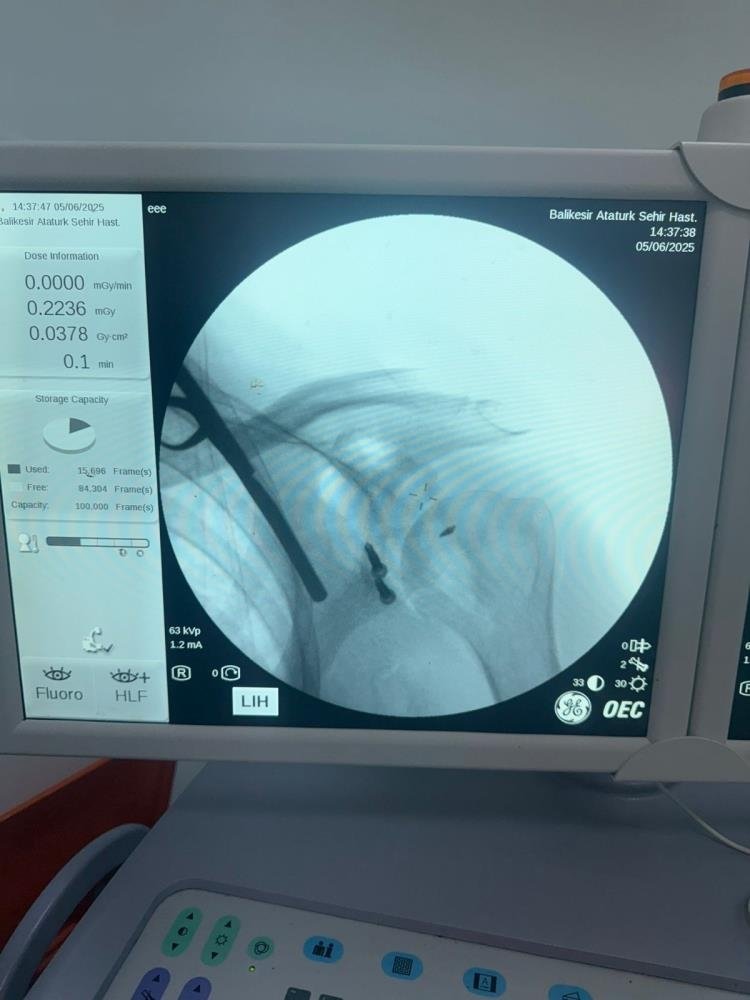

Balıkesir Atatürk Şehir Hastanesinde ilk defa Latarjet Omuz ameliyatı gerçekleştirildi. Balıkesir İl Sağlık Müdürlüğü'nden yapılan basın açıklamasında daha önceden yaklaşık on beş defa omuzu çıkan ve başka İllerde bulunan özel hastanelerde üç defa ameliyat olan hasta şikayetlerinin geçmemesi ve omuzunun tekrar çıkması üzerine Balıkesir Atatürk Şehir Hastanesi Ortopedi ve Travmatoloji Kliniğine başvurdu. Hastanın yapılan muayenesi ve tetkikleri sonucu, hastanın omuz ekleminde aşırı kemik dokusu kaybı mevcut olması sebebiyle "Latarjet omuz ameliyatı" planlandı.

Balıkesir'de ilk defa uygulanan bu yöntem Doç. Dr. Özgün Karakuş ve Op. Dr. Fatih Işık tarafından başarıyla gerçekleştirildi. Ameliyat sonrası sağlığına kavuşan hasta bir gün sonra taburcu edildi. İl Sağlık Müdürlüğü, "Ameliyat öncesi ve sonrası desteğini esirgemeyen anestezi ekibine, servis, ameliyathane ve yoğun bakım ekibine ve emeği geçen tüm çalışma arkadaşlarımıza teşekkür eder, hastamıza geçmiş olsun dileklerimizi iletiriz" açıklaması yaptı.